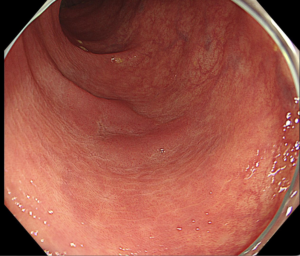

この中に「異常」があります。あなたは見つけられますか?

60代男性、便潜血陽性5年前に他院で大腸内視鏡検査の時は異常なし

画像の中に病変があります!

なんとなく赤いところわかりますか?

なんとなく盛り上がってるのわかりますか?

中央の部分に発赤調の平坦に隆起している病変が見えてきましたでしょうか。